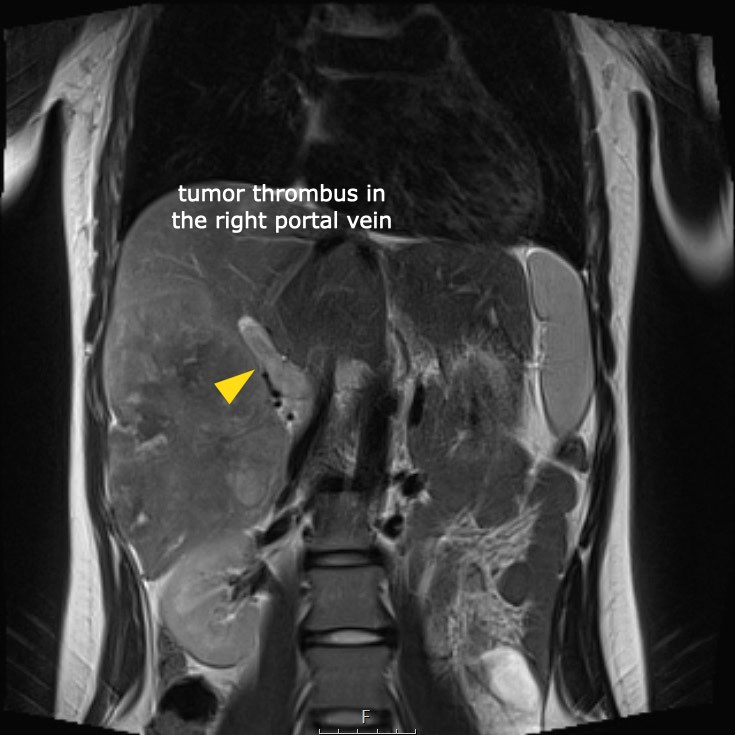

Ví dụ 1

Một bé gái 17 tuổi nhập viện với triệu chứng đau bụng vùng thượng vị. Siêu âm phát hiện một khối u gan lớn.

Trên MRI thấy khối u ở phân thùy gan 5 và 6 với các tổn thương vệ tinh ở phân thùy 7 và 8 (mũi tên). Có huyết khối u trong tĩnh mạch cửa phải (đầu mũi tên) và nhiều di căn phổi (*).